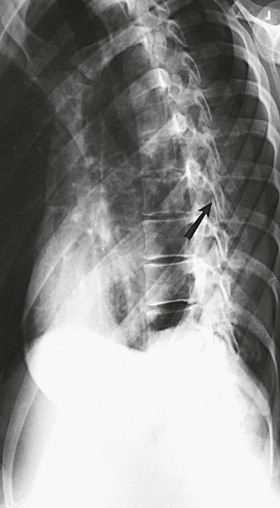

The images show oblique projections of the zygapophyseal joints (arrows on Figs. 8-81 and 8-82). The number of joints shown depends on the thoracic curve. A greater degree of rotation from the lateral position is required to show the joints at the proximal and distal ends of the region in patients with an accentuated dorsal kyphosis. The inferior articular processes of T12, having an inclination of about 45 degrees, are not shown in this projection. (See Summary of Oblique Projections on p. 382.)